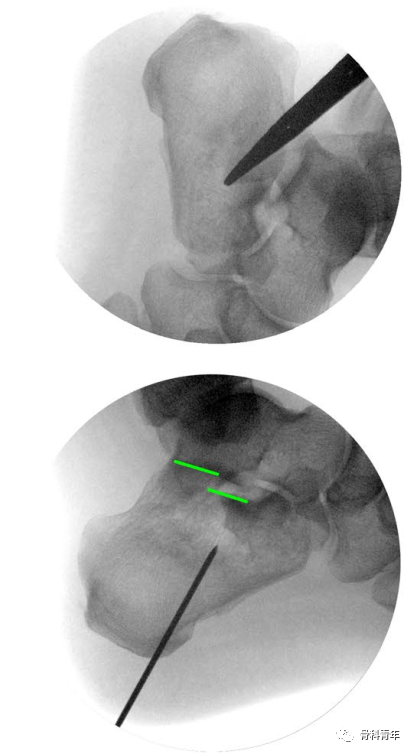

3.经克氏针,置入外套筒,将外套螺钉置入跟骨后结节骨块,螺纹不穿出骨折线;此时拔除克氏针,经外套T柄内外翻及牵引,可初步恢复内翻及高度,及松解骨块间的卡压。

4.拔除克氏针后,经外套筒置入内套,内套实心杆穿过骨折线,置入载距突骨块,并不穿出。此时内套近端螺纹与外套筒内侧螺钉咬合,转动内套T型柄,可实现内外套间的相向运动,由于外套空心螺钉固定于后结节骨块,此运动即可实现对载距突骨块撑起作用。

5.复位见关节面塌陷恢复后,克氏针临时固定,可进行后续固定操作。